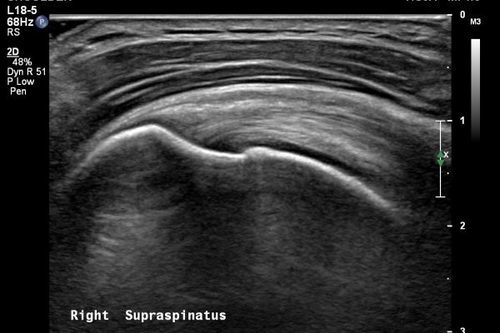

Omuz, diz vb. eklemlerin incelenmesinde ise eklem içerisinde sıvı ya da kanama varlığı, ekleme komşu kas ve tendonlardaki hasarlar, eklem komşuluğundaki kist ve kitleler değerlendirilir.